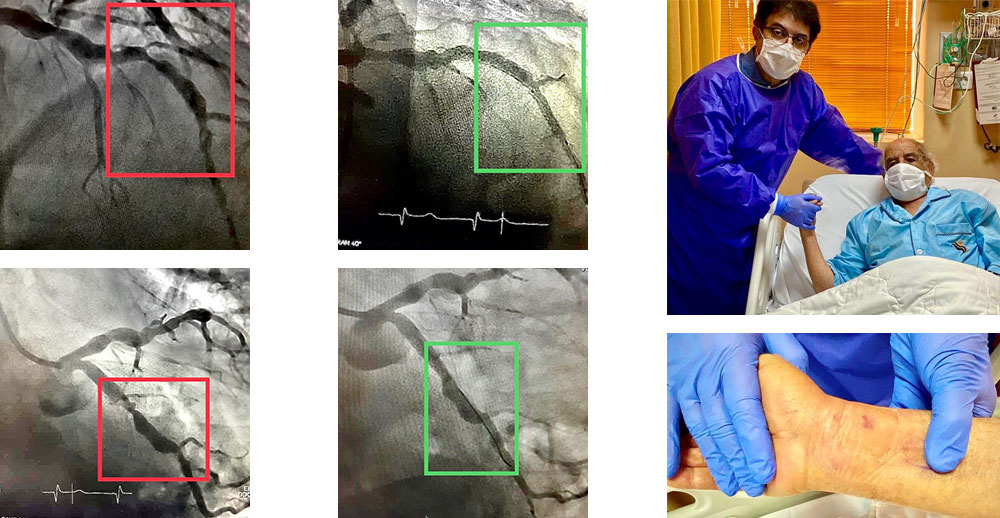

روش جدید درمان تنگی و گشادی متناوب شریان های قلب

با استنت هایی با قابلیت اتساع خود به خود، که منجر به شکل گرفتن و چسبیدن استنت در تمام طول به شدت نامنظم تنگی و گشادی رگ می شود. بیمار ۸۵ ساله ی ما، روز بعد از کارگذاری ۵ استنت در جریان آنژیوپلاستی از طریق شریان دست، قابل ترخیص است. بیمار فوق را به طور قطعی به جراحی قلب باز، ارجاع داده بودند.

بازکردن رگ اصلی و فرعی بطور همزمان با دو استنت

بیمار عزیز ما با سکته ی قلبی، روز بعد از آنژیوپلاستی با عروق باز شده آماده ی ترخیص است.